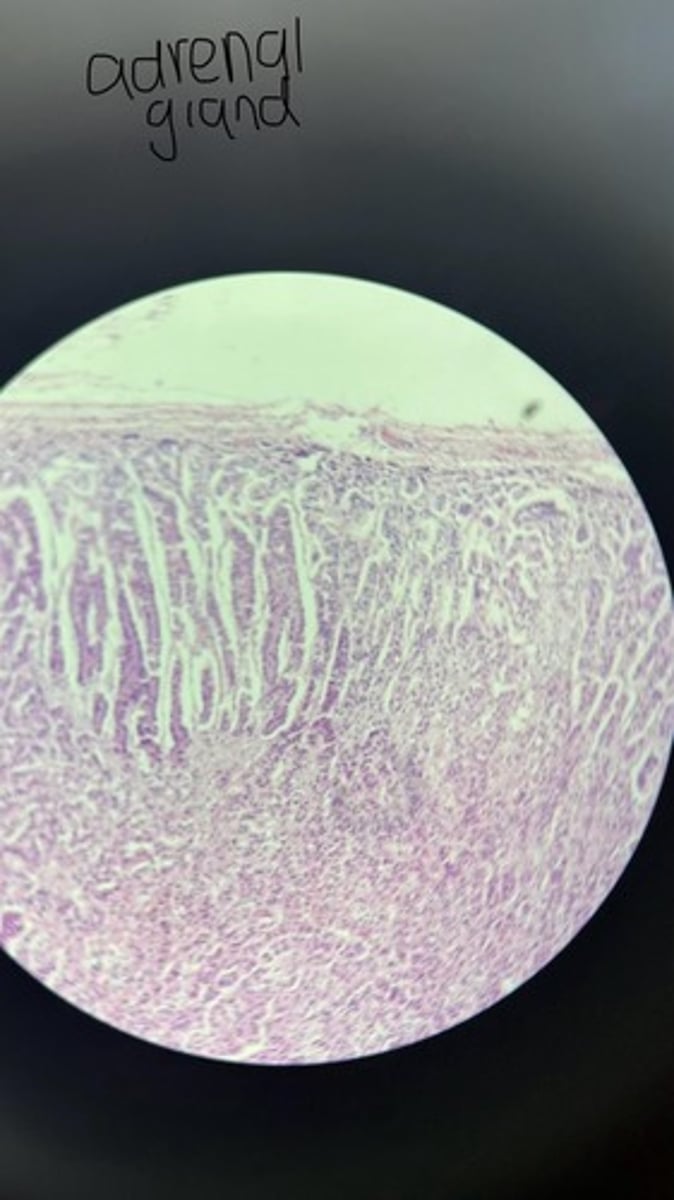

Adrenal gland HE

Adrenal gland HE

Adrenal gland HE

Adrenal gland HE

Adrenal gland

Adrenal gland HE